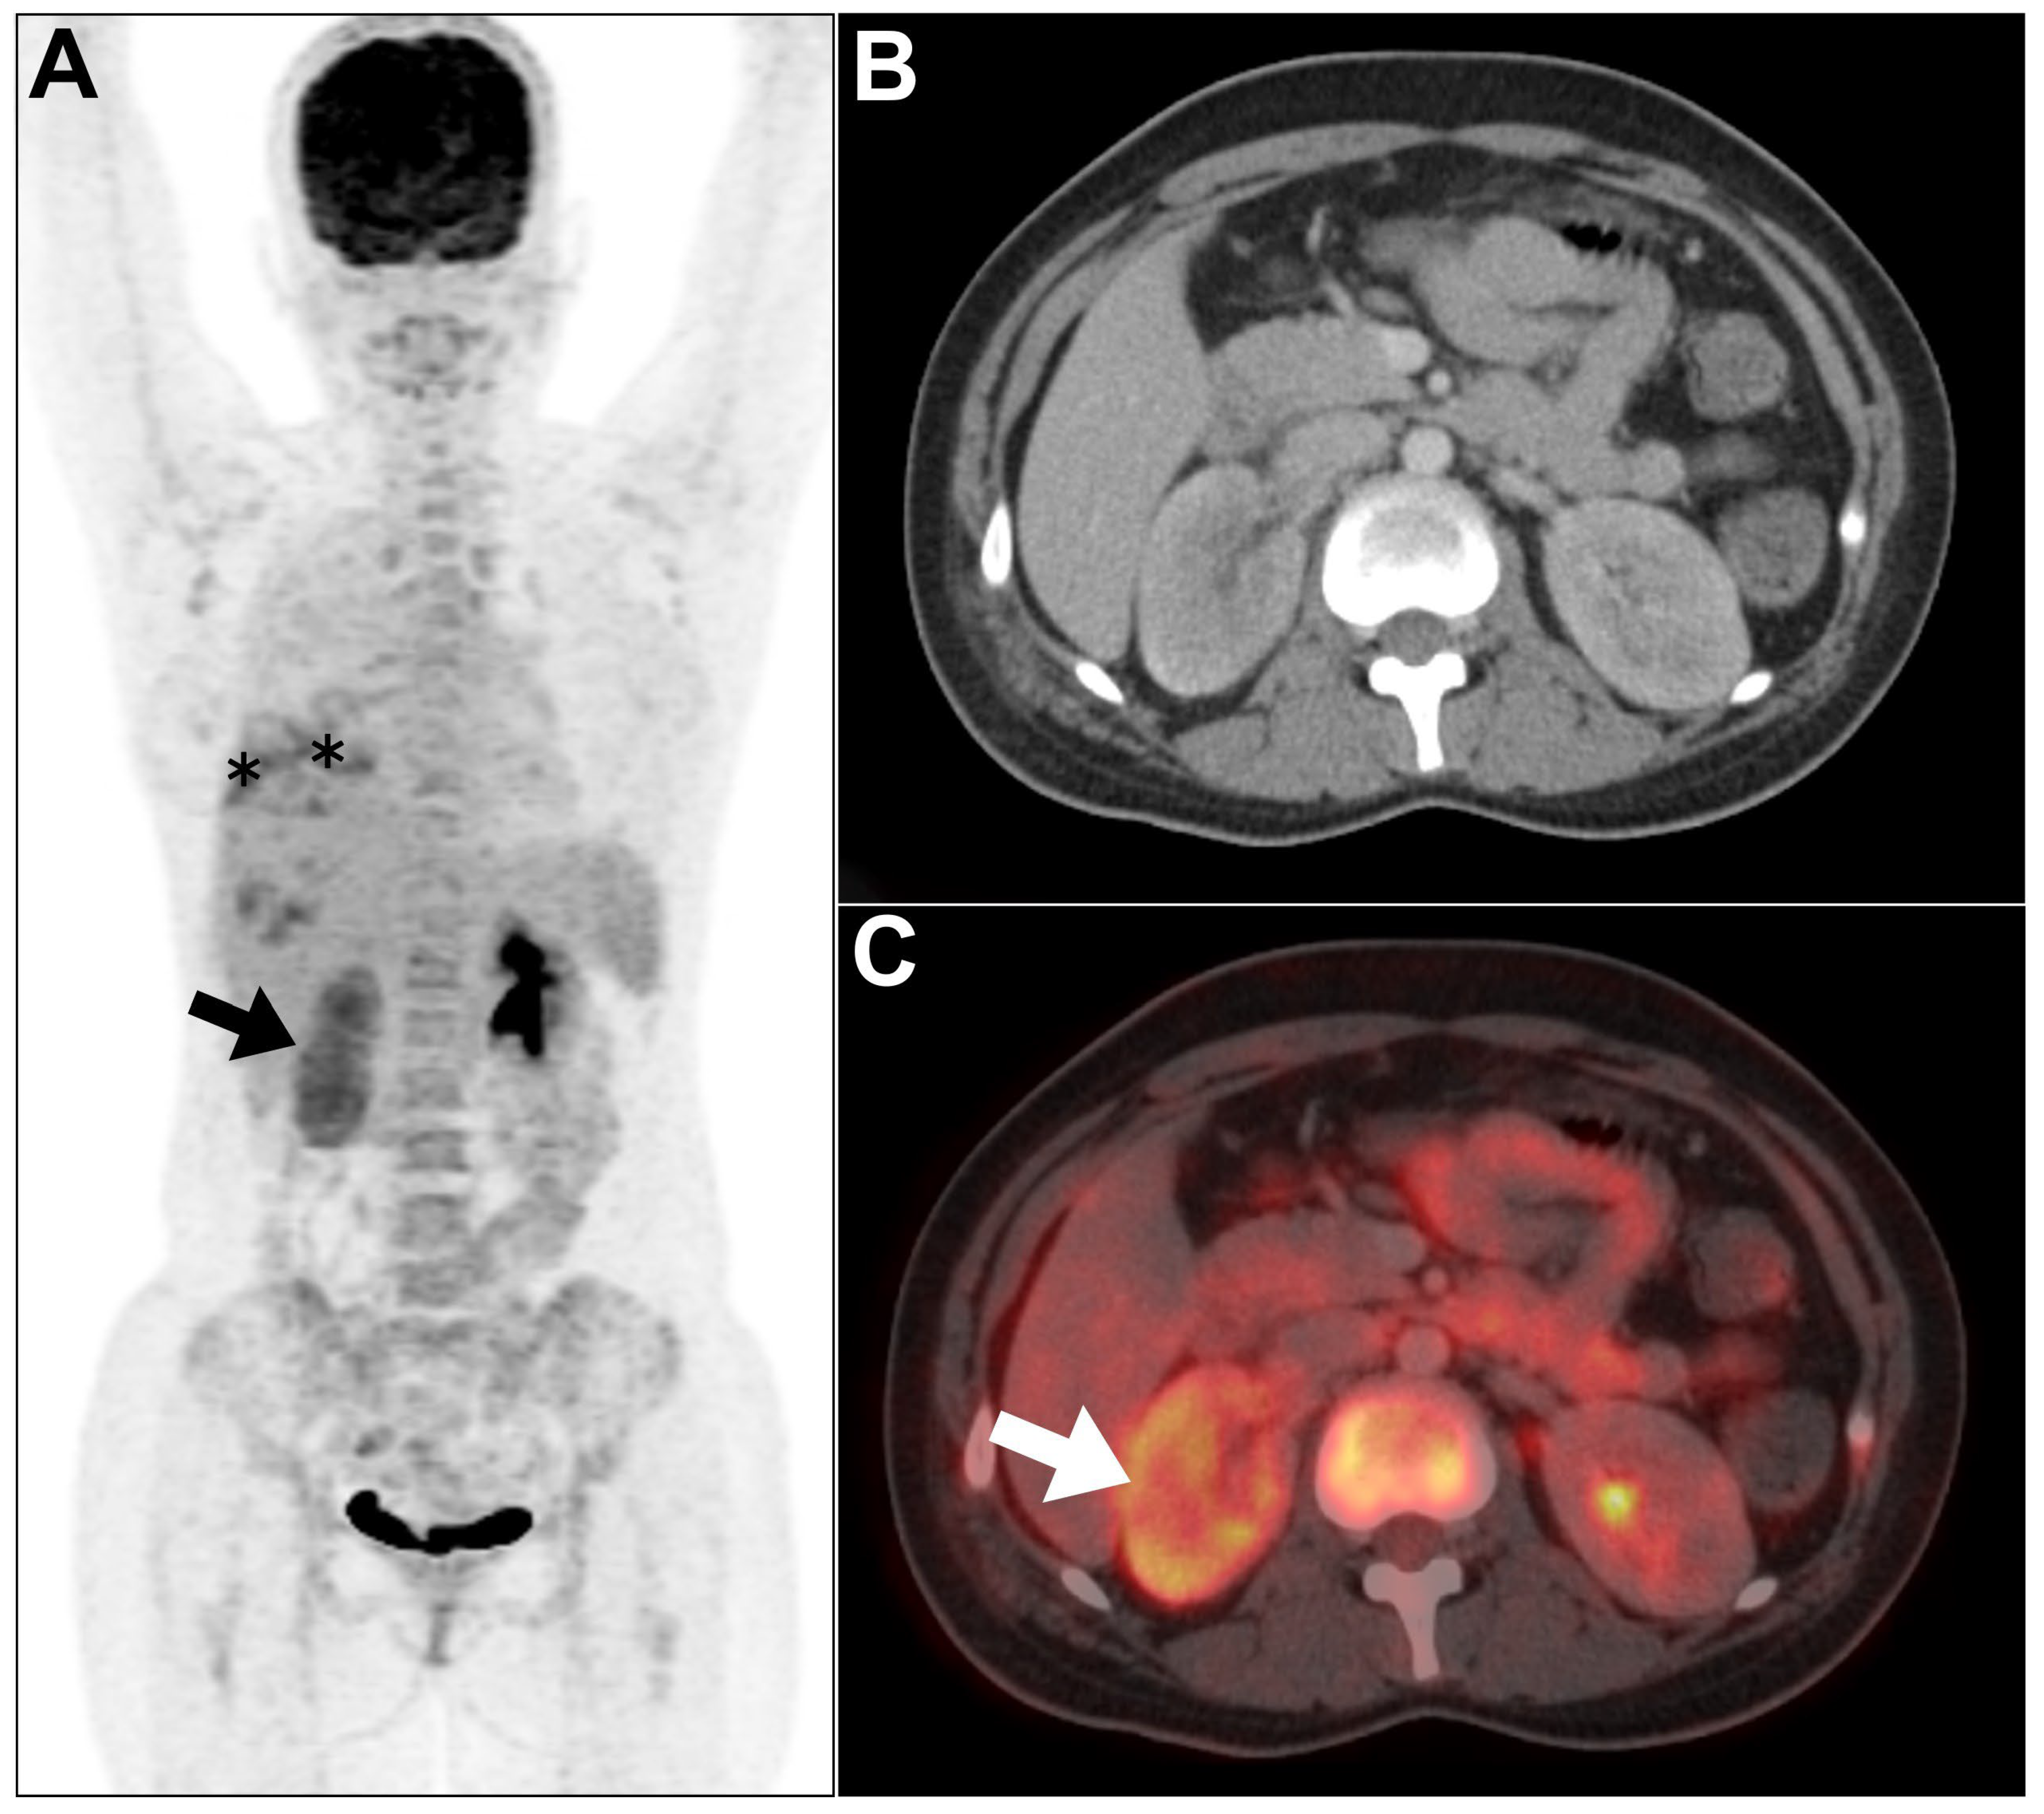

- Pijl, J.P.; Glaudemans, A.W.; Slart, R.H.; Kwee, T.C. 18F-FDG PET/CT in autosomal dominant polycystic kidney disease patients with suspected cyst infection. J. Nucl. Med. 2018, 59, 1734–1741. [Google Scholar] [CrossRef]

- Ronsin, C.; Bailly, C.; Le Turnier, P.; Ville, S. Value of FDG-PET/CT in monitoring cyst infections in patients with autosomal dominant polycystic renal disease. Clin. Kidney J. 2021, 14, 2273–2275. [Google Scholar] [CrossRef]

- Bobot, M.; Ghez, C.; Gondouin, B.; Sallée, M.; Fournier, P.-E.; Burtey, S.; Legris, T.; Dussol, B.; Berland, Y.; Souteyrand, P. Diagnostic performance of [18F] fluorodeoxyglucose positron emission tomography–computed tomography in cyst infection in patients with autosomal dominant polycystic kidney disease. Clin. Microbiol. Infect. 2016, 22, 71–77. [Google Scholar] [CrossRef]